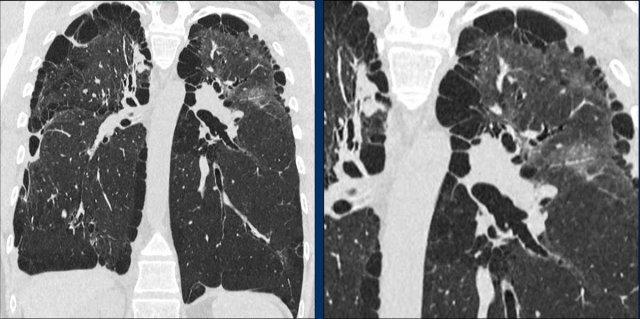

Hình ảnh

- Các nang có hình dạng kỳ dị ở một bệnh nhân nam mắc LCH.

- Trường hợp nặng của LCH giai đoạn tiến triển, hình ảnh tương tự khí phế thũng. Ở một bệnh nhân nữ không có tiền sử hút thuốc, đây cũng có thể là trường hợp LAM (bệnh cơ trơn bạch huyết) nặng.

- Nhiều nốt, một số đang tạo hang, với phân bố ưu thế ở vùng phổi trên (khác với di căn), và hoàn toàn không tổn thương các ngách màng phổi.

- Sự kết hợp giữa các nang kỳ dị, các nốt và các nốt đang tạo hang với phân bố ưu thế ở vùng phổi trên.

Đây là hình ảnh của một bệnh nhân nam 66 tuổi, có tiền sử hút thuốc lá và đến khám vì triệu chứng khó thở.

Nhận xét hình ảnh

Ghi nhận nhiều nang.

Một số có hình dạng bất thường và một số có dấu hiệu “cheerio” (hình vòng tròn) do hiện tượng tạo hang bên trong nốt (mũi tên trắng).

Ngoài ra còn ghi nhận một số nốt (mũi tên đen).

Bình luận

Sự kết hợp của các dấu hiệu này trên một bệnh nhân hút thuốc lá là điển hình cho chẩn đoán LCH.

Tiếp tục…

Trên tái tạo mặt phẳng coronal, có thể thấy rõ ràng rằng các nang chủ yếu tập trung ở thùy trên và thùy giữa, trong khi vùng đáy phổi được bảo tồn.

Đặc biệt khi LCH còn ở giai đoạn nốt, sự phân bố này có thể là dấu hiệu hữu ích trong việc phân biệt với di căn phổi, vốn có xu hướng ưu thế ở thùy dưới.

Đây là một trường hợp tương tự.

Lưu ý rằng các nang chủ yếu tập trung ở thùy trên và thùy giữa.

Các ngách màng phổi được bảo tồn.

Các nang đã gây ra tràn khí màng phổi.